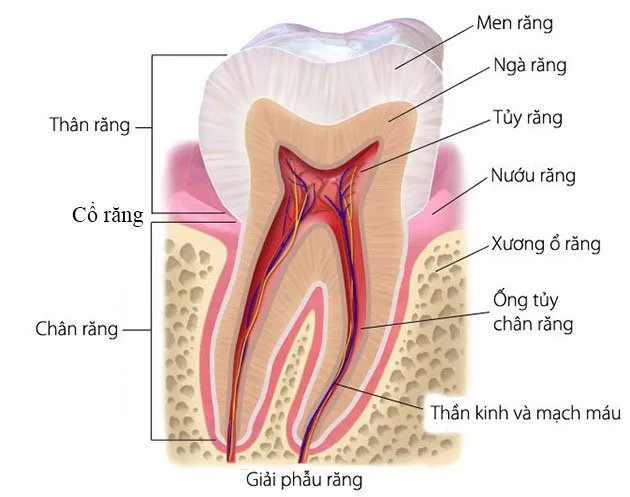

Các răng không chỉ giữ vai trò quan trọng trong việc ăn nhai mà còn góp phần tạo nên vẻ đẹp thẩm mỹ và sự tự tin